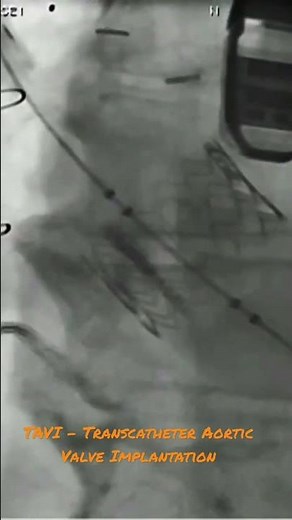

Minimally Invasive Aortic Valve Replacement for Aortic Stenosis: Edwards Valve

YouTubeMichigan Medicine